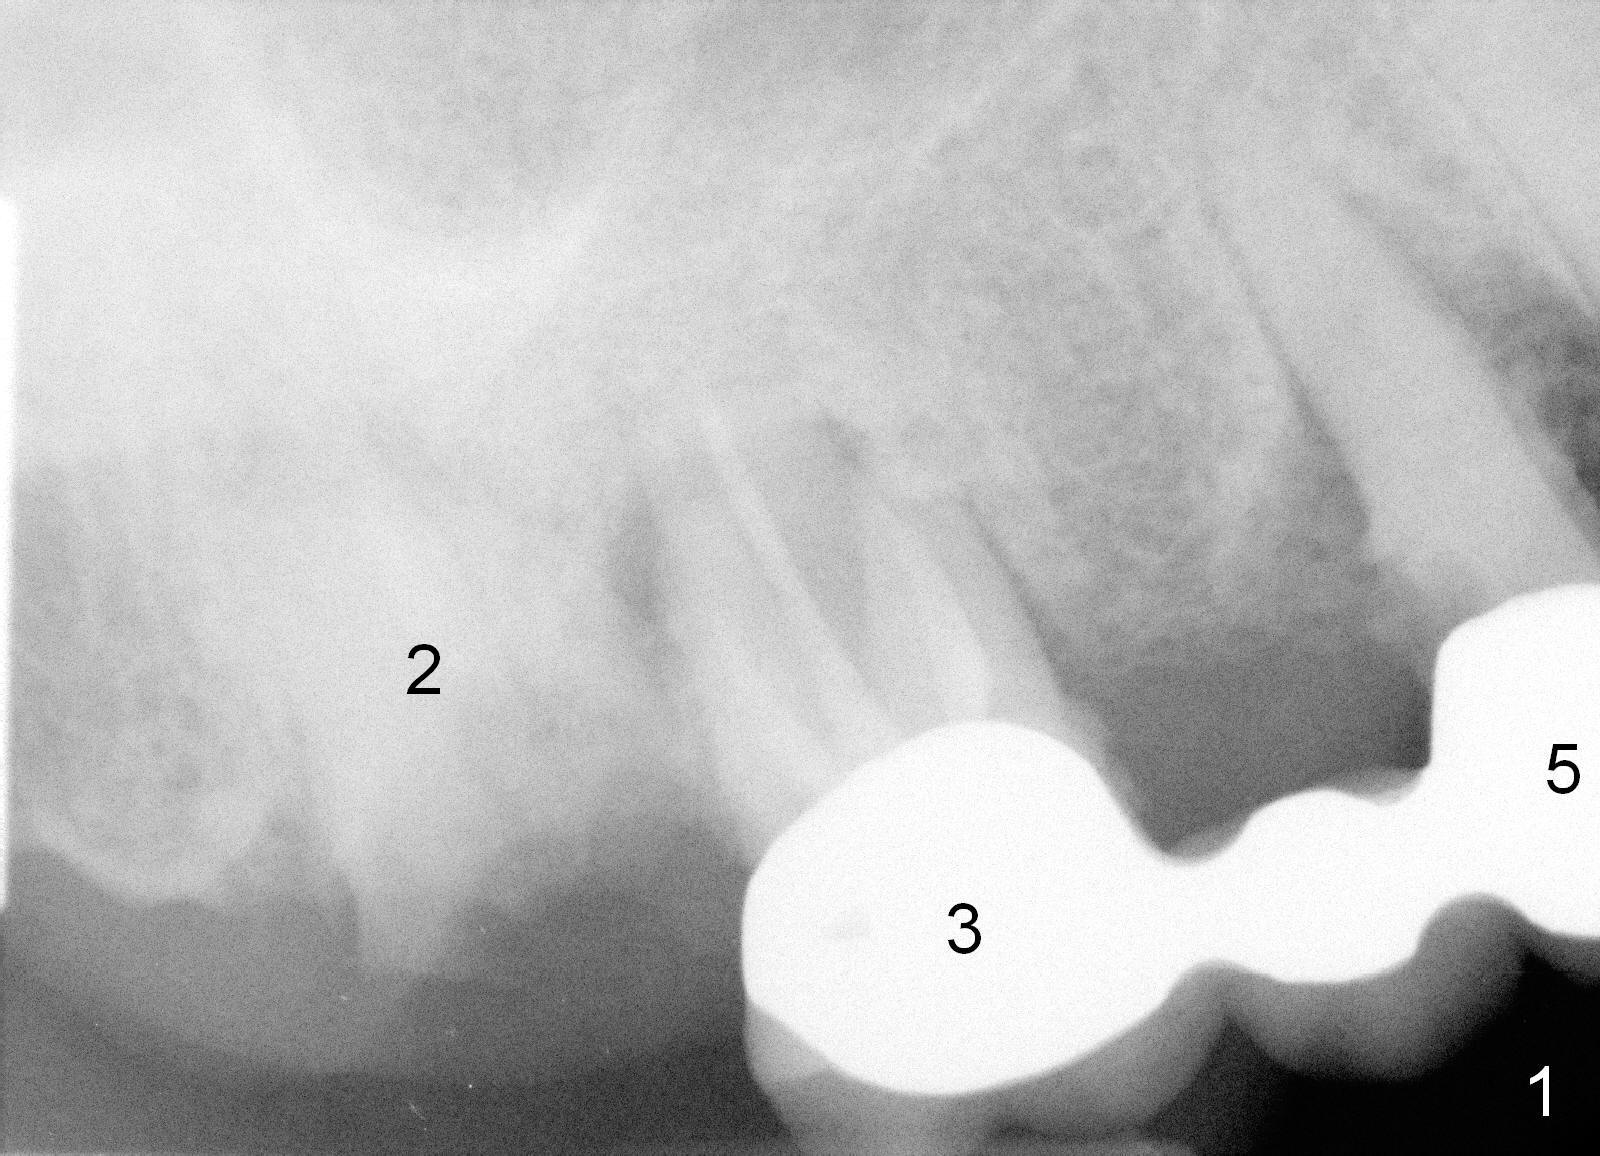

A 78-year-old lady (YT) has had poor dentition. The tooth #2 fractured 3 years ago (Fig.1). Now bone loss around the abutments for the bridge at #3-5 is more severe (Fig.2). There is an abscess palatal to the tooth #5. After extraction, the socket at #3 should be large (treated with 2% Xylocaine/1:50,000 Epinephrine). An extra wide implant is expected. Since there is more than 12 mm of bone in height (Fig.3), a UF implant is the most appropriate (6, 6.5 or 7x12 mm, Fig.4). The longest extra wide SM implant is 10 mm.

Fig.5 was taken 8 months post #2 ext. In fact the upper left bridge lost 4 months ago.